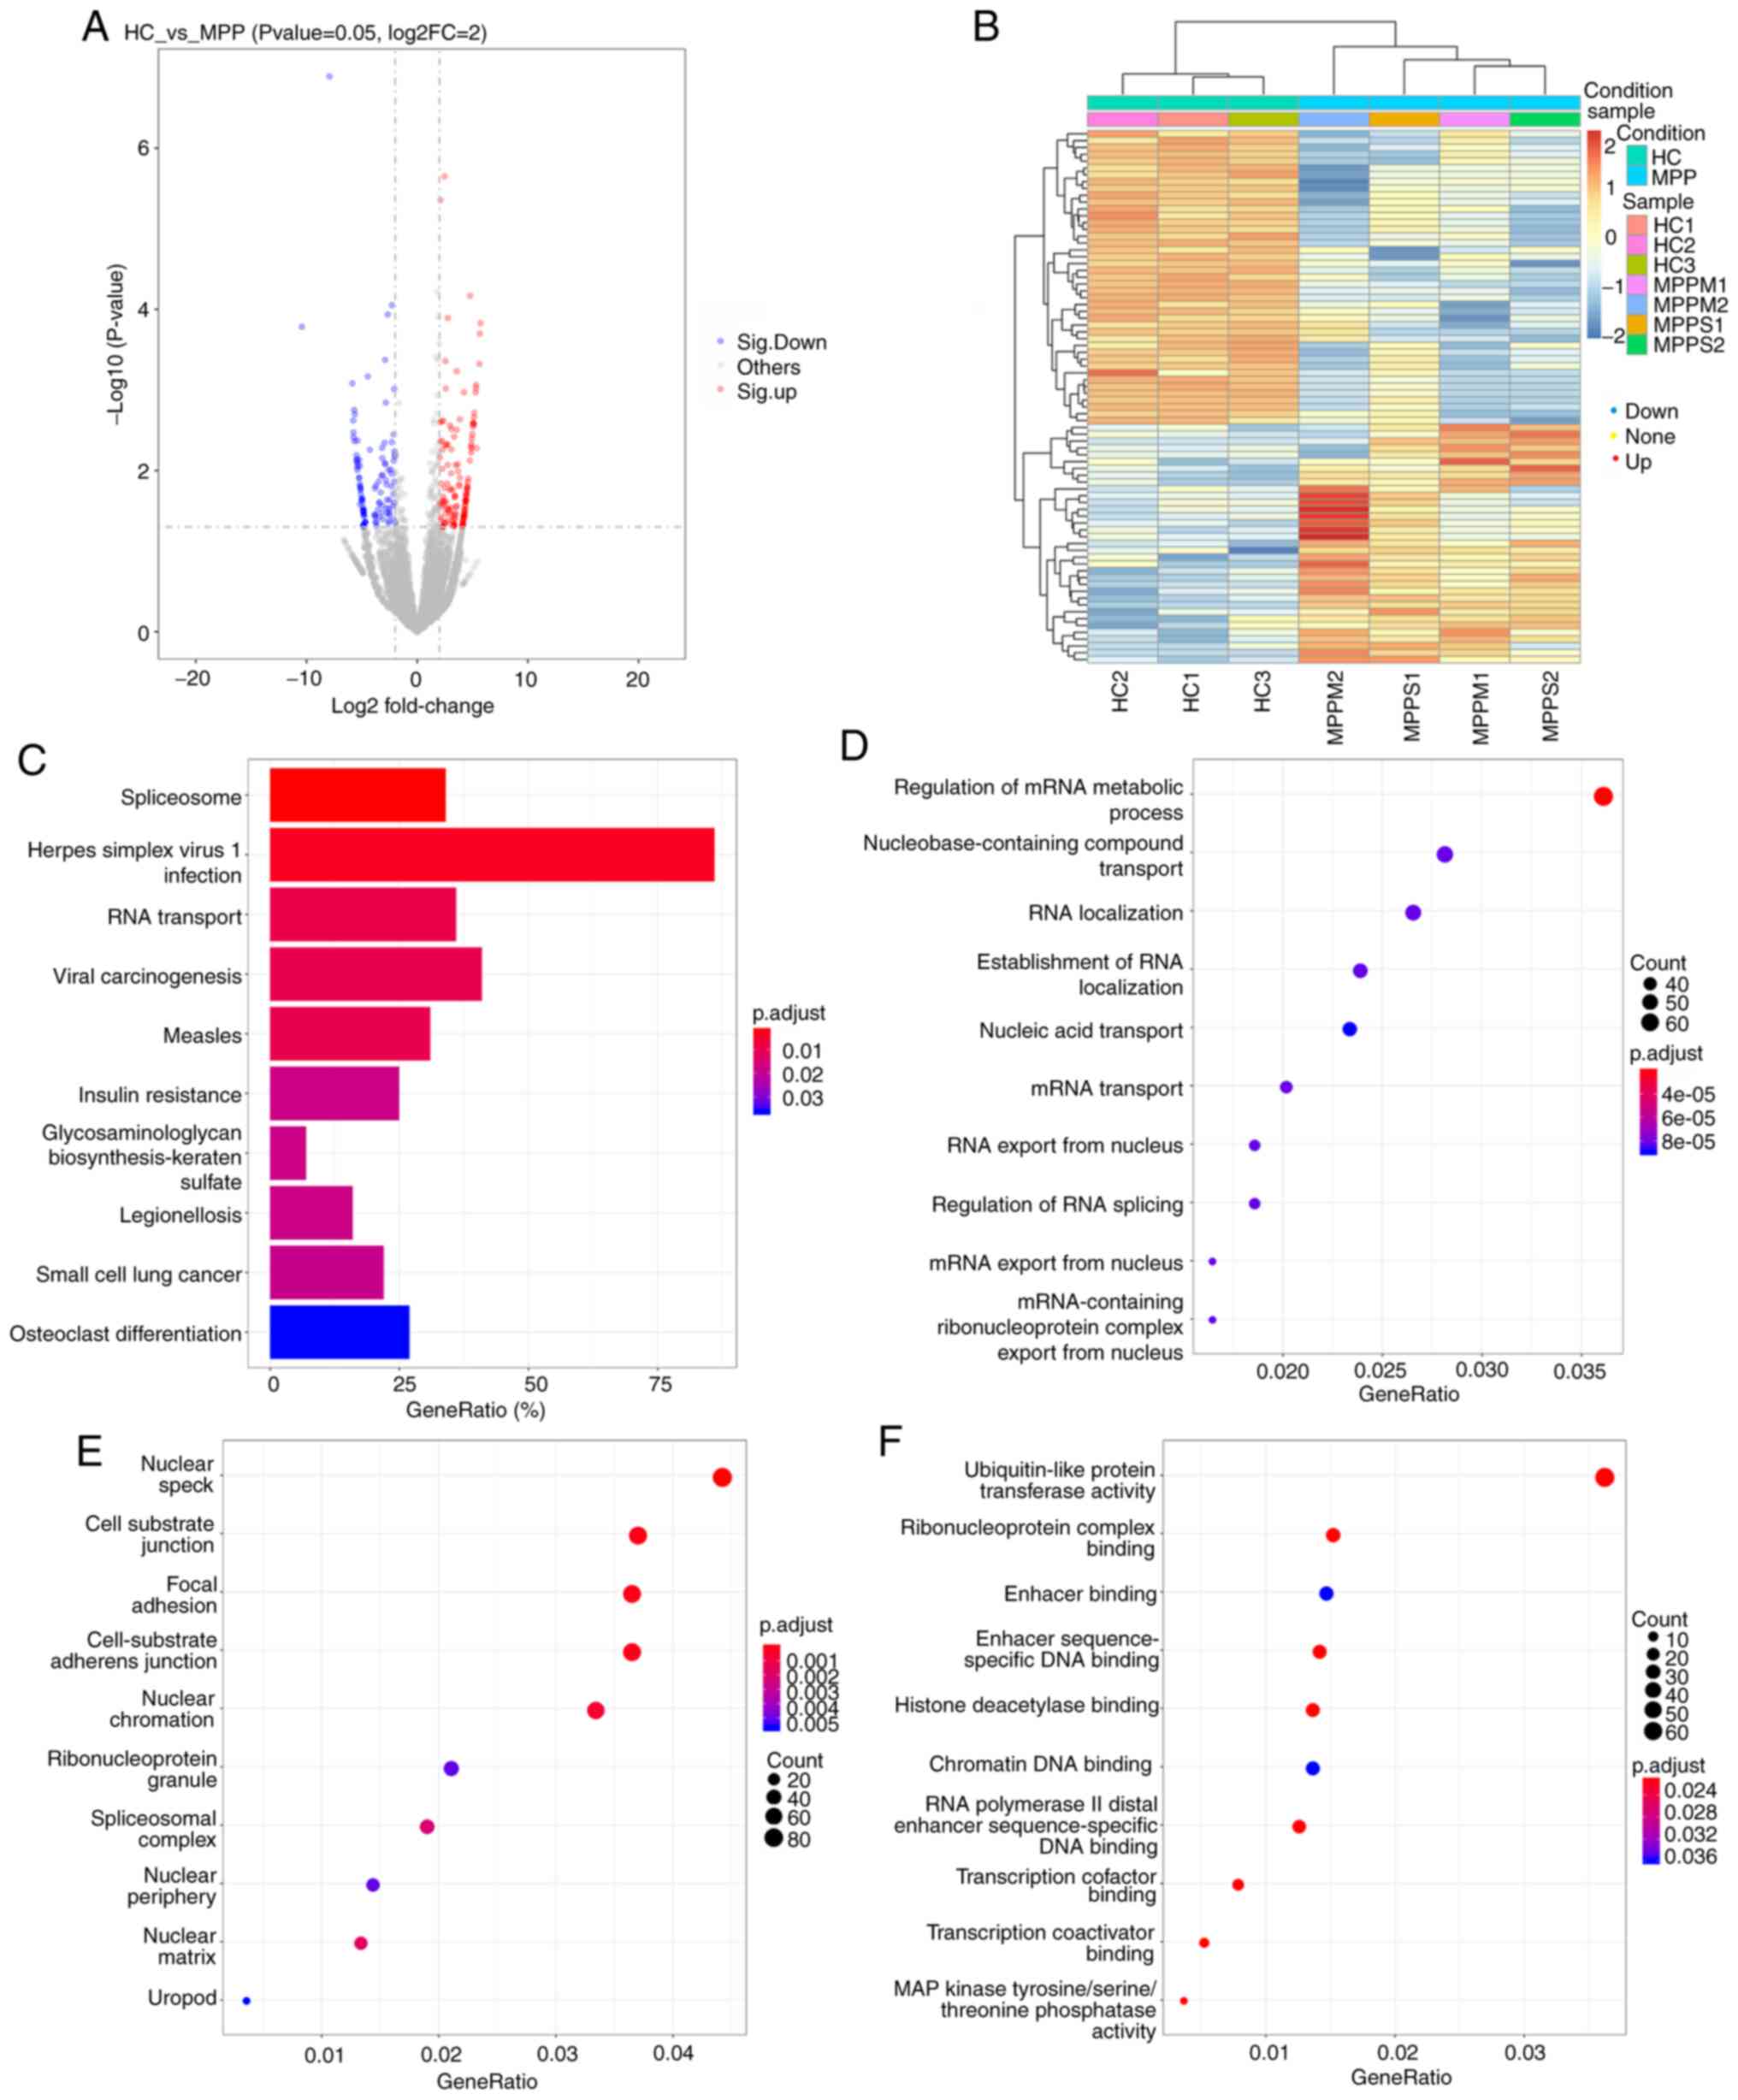

A total of 611 lncRNAs (416 upregulated and 195 downregulated) and 692 mRNAs (598 upregulated and 94 downregulated) were significantly differentially expressed (P<0.05) between the NRMPP and HC groups (Fig. 3). A total of 937 lncRNAs (433 upregulated and 504 downregulated) and 1,027 mRNAs (593 upregulated and 434 downregulated) were significantly differentially expressed (P<0.05) between the RMPP and HC groups. A total of 17 lncRNAs (4 upregulated and 13 downregulated) and 18 mRNAs (6 upregulated and 12 downregulated) were significantly differentially expressed (P<0.05) between the RMPP and NRMPP groups (Table III). The significantly differentially expressed lncRNAs between the RMPP and NRMPP groups included ENSG00000249790, ENSG00000261026, MSTRG.215206, MSTRG.233743, MSTRG.238033, MSTRG.238419, MSTRG.268000, MSTRG.275241 (Table III).

In the circRNA/miRNA co-expression analysis, a total of 1,370 circRNAs (505 upregulated and 865 downregulated) were significantly differentially expressed (P<0.05) between the HC and MPP groups (Fig. 5A and B). The functions of circRNAs were associated with the known function of the host linear transcripts and annotated by the GO and KEGG databases. In the GO analysis of the host linear transcripts, the differentially expressed terms were classified into three categories. Under biological processes, the GO terms were primarily enriched in ‘regulation of mRNA metabolic process’, ‘nucleobase-containing compound transport’ and ‘RNA localization’ (Fig. 5D). Under the category of cellular component, the GO terms were primarily enriched in ‘nuclear speck’, ‘cell-substrate junction’ and ‘focal adhesion’ (Fig. 5E). Under the category of molecular function, the GO terms were primarily enriched in ‘ubiquitin-like protein transferase activity’, ‘ribonucleoprotein complex binding’ and ‘enhancer binding’ (Fig. 5F). In the KEGG pathway analysis, the significant DEGs were primarily enriched in ‘Herpes simplex virus 1 infection’, ‘viral carcinogenesis’ and ‘RNA transport’ (Fig. 5C). The top 11 significantly differentially expressed circRNAs between the HC and MPP groups are listed in Table V.